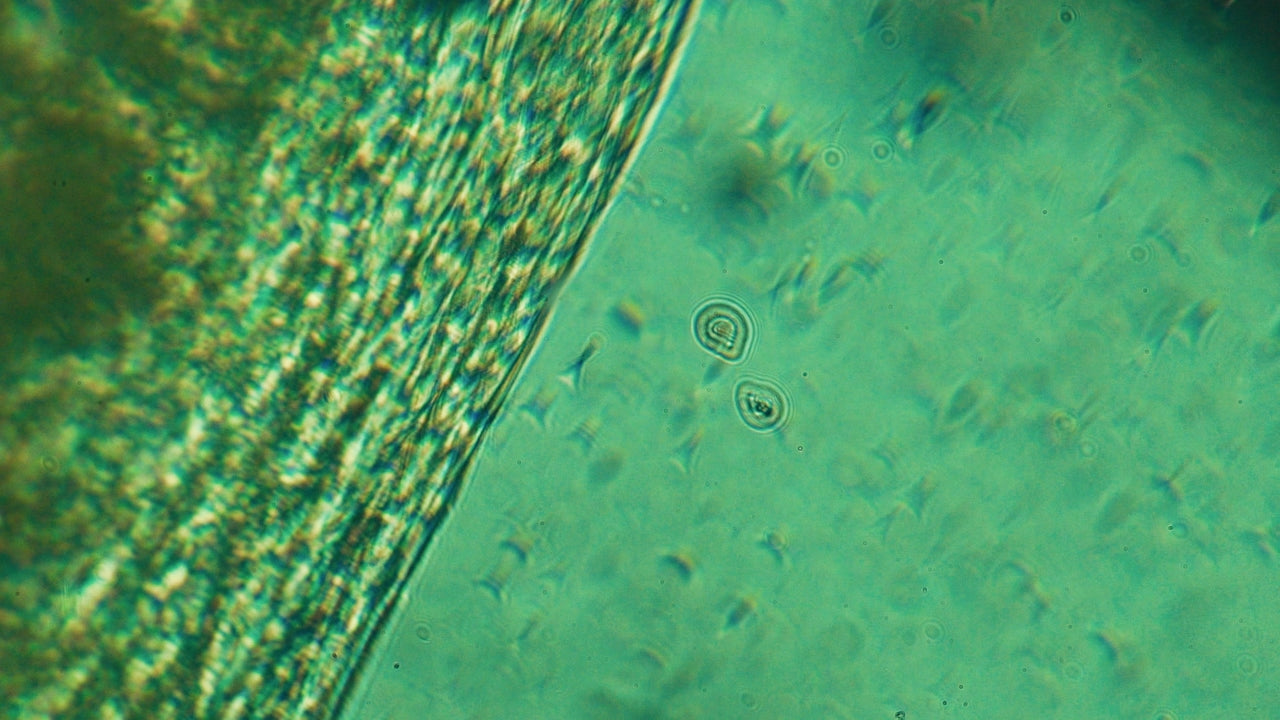

The test analyses all the DNA in your stool to identify thousands of gut microbes — including bacteria, fungi, and viruses — and the genes they carry. It measures:

- Microbial composition: which species and strains live in your gut

- Functional activity: what those microbes are doing (e.g. digestion, vitamin production, inflammation control)

- Gut health markers: balance, diversity, and presence of harmful or beneficial species

- Metabolic pathways: including those linked to short-chain fatty acids, bile acids, and GLP-1 stimulation